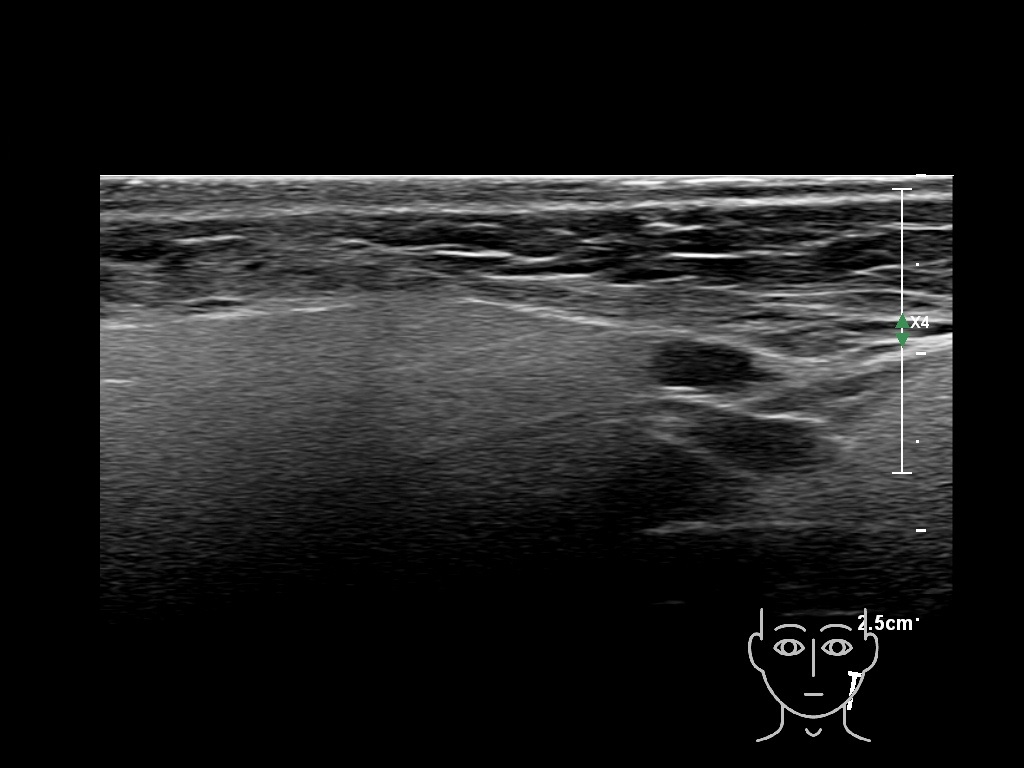

Filler injections in the parotid gland may go unnoticed, however, inflammatory reactions and abscesses may occur. Hypervascularity can be seen with color doppler. Filler deposits are supposed to be injected into the superficial fatty layer . The space to inject into this layer may be limited. Routinely we measure a width of 2-4 millimeters with sometimes subcutaneous layers being less than one millimeter thick.

Study the first image to recognize the different layers. If you are sure about the layers, swipe to the second image to view the answer (if applicable).